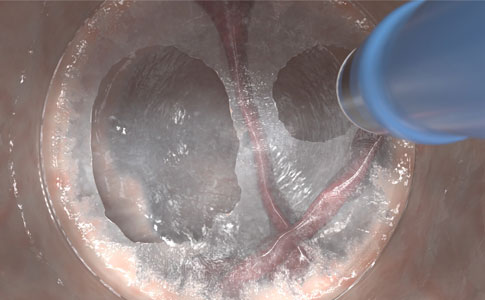

TAGLIARE E COAGULARE CON PRECISIONE

Raggiungete un'elevata precisione elettrochirurgica con danni termici limitati grazie all'elettrodo sottile e applicate varie tecniche di coagulazione con le modalità VIO®.

- Elettrodo sottile da 0,5 mm per un taglio preciso con danni termici limitati

- Particolarmente importante per l'anatomia a parete sottile, ad esempio il colon destro

- Isolamento ed esposizione della vascolarizzazione e compressione dei vasi sanguigni, riducendo il rischio di emorragie.